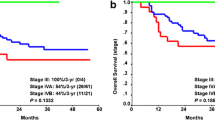

The multivariable CoxBoost analysis (Table 4), combining all modalities and clinical parameters, showed that HPV status, intoxications, ADCGTV, Ktrans, and Ve remained predictive for LRF (C-index of 0.546). The log-rank test (Fig. 2) showed that these risk factors were significantly predictive (p = 0.023) for LRF (Fig. 2b), whereas risk stratification per T-stage (Fig. 2a) was not significantly predictive (p = 0.92).

Kaplan-Meier survival curves, which show the recurrence-free survival stratified for (a) T-stage and (b) for the recurrence risk score. In a, the recurrence-free survival is shown, which is not significantly predictive. In b, patients were given a risk score by the amount of risk factor points. These risk factors (each with a score of 1 point) were summed up when the predictive quantitative parameters that are higher than the median value of the quantitative parameter or positive clinical parameter (HPV, intoxications, hypopharyngeal PT location or N-stage > 1). The median value of quantitative parameters was calculated based on all included patients. This risk score stratification system is found significantly predictive. In c, the overall survival is shown, which is stratified for T-stage, which is not significant predictive. In d, the overall survival is shown, stratified for the risk score groups, which is found significantly predictive

Predictive parameters scored as risk factors for OS (Fig. 2) were significantly predictive (p = 0.046) in the log-rank test (Fig. 2d) when combined, whereas risk stratification per T-stage (Fig. 2c) was found not significant (p = 0.188).